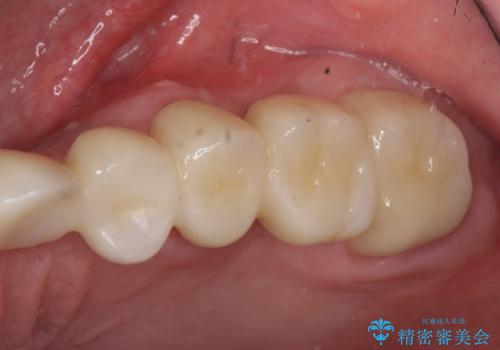

インプラントは希望されなかったため、左側は1番から7番のロングスパンブリッジによる補綴を行いました。

オールセラミッククラウンについて

今回用いたオールセラミッククラウンは、ジルコニアフレームという白い素材の上にセラミックを盛っているため審美性が非常に高いのが特徴です。

またジルコニアは人工ダイヤモンドの材料にも使われているほど高い強度を持っており、そのためオールセラミッククラウンは審美性だけでなく、奥歯やブリッジの補綴も可能とするクラウンです。